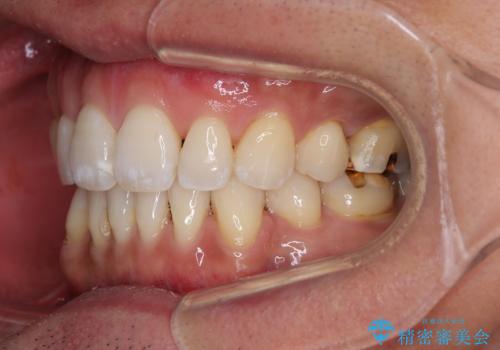

- 口元の突出感を気にして来院された患者様です。

強い咬合力と上顎前歯の傾斜により前歯が突出し、唇が閉じにくい状況であったため、上下左右の第一小臼歯4本を抜歯し、ワイヤー装置にて矯正治療を行うこととしました。

非常に咬合力が強いため、抜歯したスペースが閉じるのか不安でしたが、順調に歯が移動し、予定よりも早く治療を終えることができました。